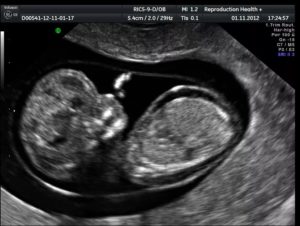

УЗИ плода – основной диагностический метод. Основные признаки УЗИ:

- излишек амниотической жидкости;

- нарушение нормы габаритов ребенка из-за отечности, увеличение размера живота по сравнению с размером головки;

- увеличенные габариты сердца, кардиомегалия;

- увеличенные размеры печени и селезенки;

- отведенные в разные стороны конечности с вспухшим животом «Поза Будды»;

- последствия заболевания.

Главным диагностическим методом служит УЗИ плода. К УЗИ-признакам относятся:

- отечность плаценты («толстая плацента»);

- избыток амниотической жидкости (многоводие);

- размеры плода больше нормы из-за отека (в частности увеличенные размеры живота вследствие асцита по сравнению с размерами головки);

- скопление жидкости во всех полостях плодового организма (гидроперикард, асцит, гидроторакс)

- отек подкожно-жирового слоя в виде двойного контура;

- отек кожи головы, рук и ног;

- кардиомегалия (увеличение размеров сердца);

- утолщение кишечника (отек стенок);

- увеличение печени и селезенки (гепатоспленомегалия)

- «поза Будды» — раздутый живот с отведенными от него конечностями и позвоночником;

- низкая двигательная активность в сочетании с другими признаками.